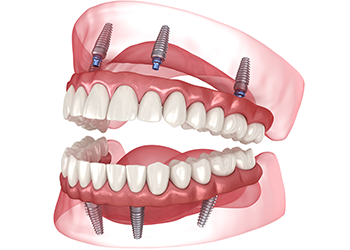

オールオン4(All-on-4)

片顎わずか4本のインプラントで

12本の歯を支えることが可能です

総入れ歯の方や残存歯が少ない方に適した治療方法です。4本(症例によっては6本)のインプラントで最大12本の人工歯を支えることができ、治療本数を抑えることで手術や経済的な負担を軽減できます。通常のインプラントと同様の使用感で、しっかりと咬むことが可能です。あごの骨が痩せている場合でも、手術が行えるケースがあります。

オールオン4

最小4本のインプラントで力を分散し、人工歯をしっかり支えます。必要に応じて本数が増える場合もありますが、従来の治療に比べ、身体的・経済的・時間的な負担を大幅に軽減できます。